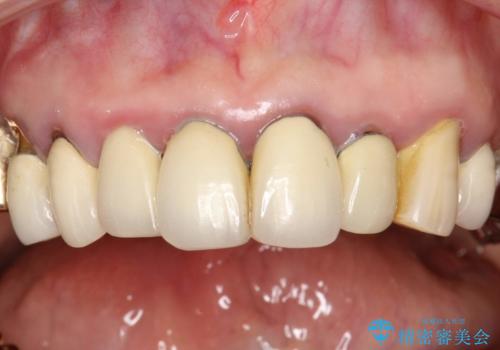

前歯の低クオリティな治療の実態 妥協無い治療で根本からやり治す

・虫歯がとりきれていない

・接触部分がガタガタで適合の悪い金属

・全く無菌の努力がされていない根管治療

など、いい加減な治療は「治療」ではなく、むしろ医原性に歯の寿命を短くします。

最もよくないのは、クオリティの低い治療を何度も繰り返すことです。